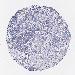

CERVICAL CANCER - Protein expressioni

A mouse-over function shows sample information and annotation data. Click on an image to view it in a full screen mode. Samples can be filtered based on level of antibody staining by selecting one or several of the following categories: high, medium, low and not detected. The assay and annotation is described here.

Note that samples used for immunohistochemistry by the Human Protein Atlas do not correspond to samples in the TCGA dataset.

Antibody stainingi

Antibody staining in the annotated cell types in the current human tissue is reported as not detected, low, medium, or high, based on conventional immunohistochemistry profiling in selected tissues. This score is based on the combination of the staining intensity and fraction of stained cells.

Each image is clickable and will lead to virtual microscopy that enables deeper exploration of all samples and also displays staining intensity scores, fraction scores and subcellular localization as well as patient and tissue information for each sample.

Antibody CAB002973

Squamous cell carcinoma, NOS